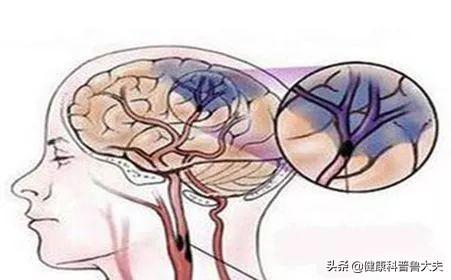

Notre cerveau gère presque toutes les fonctions de notre corps et est connu comme le commandant du corps. Le cerveau dépend du sang pour transporter l'oxygène et les nutriments dont il a besoin. Lorsque les vaisseaux sanguins sont bloqués pour diverses raisons, le cerveau est incapable d'obtenir de l'oxygène et des nutriments et meurt, entraînant la perte de fonctions de notre corps, ce qui est appelé infarctus cérébral. Les fonctions des différentes parties du cerveau étant différentes, les patients auront des séquelles plus ou moins importantes selon la localisation et l'étendue de la nécrose. Certaines personnes peuvent n'avoir qu'un léger vertige et découvrir qu'elles ont subi un infarctus cérébral lorsqu'elles se rendent à l'hôpital pour un examen (la plupart des patients atteints d'infarctus cérébral lacunaire sont découverts au cours de l'examen). Certains patients garderont des séquelles telles que l'hémiplégie, l'immobilité, la cécité, le retard mental, voire la mort.

L'infarctus cérébral est en fait un trouble de l'irrigation sanguine des vaisseaux sanguins du cerveau, qui se traduit par une irrigation sanguine insuffisante du cerveau, ce qui déclenche l'ischémie et l'hypoxie et aggrave encore la nécrose ischémique ou le ramollissement du tissu cérébral. L'infarctus cérébral représente la majorité des accidents vasculaires cérébraux dans la pratique clinique, et les types d'accidents vasculaires cérébraux les plus courants sont les suivantsThrombose cérébrale, infarctus lacunaire et embolie cérébraleetc.

L'infarctus cérébral est divisé en plusieurs types en fonction des différentes causes de l'infarctus : la rupture de la plaque causée par l'athérosclérose, formant un thrombus qui bloque les vaisseaux sanguins cérébraux, forme un infarctus cérébral ; l'embolie formée dans la région du cœur en raison d'une fibrillation auriculaire, d'un flutter auriculaire, d'une insuffisance cardiaque, d'une maladie valvulaire cardiaque, etc., qui pénètre dans les vaisseaux sanguins cérébraux avec le flux sanguin pour bloquer les vaisseaux sanguins cérébraux, forme également un infarctus cérébral ; l'occlusion des petits vaisseaux sanguins des artères cérébrales en raison d'un durcissement et de lésions, etc. forme également un infarctus cérébral, et ces infarctus cérébraux se produisent lentement en termes de pathogenèse. Ces infarctus cérébraux, bien qu'ils soient lents à se produire, mais lorsque les vaisseaux sanguins cérébraux sont soudainement bloqués, en particulier les vaisseaux sanguins importants responsables de l'approvisionnement en sang du cerveau, l'infarctus cérébral se produit d'un seul coup et il n'y a pas trop de précurseurs pour que nous puissions y faire face. L'infarctus cérébral se produit directement lorsqu'il entraîne directement dans le corps une hémiplégie, une aphasie, une ataxie, qui peuvent être accompagnées de maux de tête sévères, de nausées, de vomissements et d'autres symptômes, et l'état peut rapidement évoluer vers un infarctus cérébral. Par conséquent, pour prévenir l'infarctus cérébral, nous devrions toujours contrôler activement le risque à partir de la pathogenèse, et l'idée de se fier aux précurseurs ou aux symptômes précoces pour juger du risque d'infarctus cérébral est très difficile à mettre en œuvre pour prévenir le risque et intervenir à l'avance.

L'infarctus cérébral est également appeléInfarctus cérébral ou accident vasculaire cérébral ischémique (AVC ischémique cérébral)Ce terme désigne la nécrose ou le ramollissement du tissu cérébral dû à un manque d'apport sanguin au cerveau, qui se produit à la suite d'une ischémie ou d'une hypoxie.